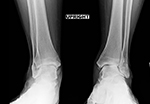

Our standing xray protocol is used to determine the overall shape, structure and integrity of the ankle and foot, while facilitating a comparison with the opposite side. The x-rays also assist in the evaluation of associated conditions.